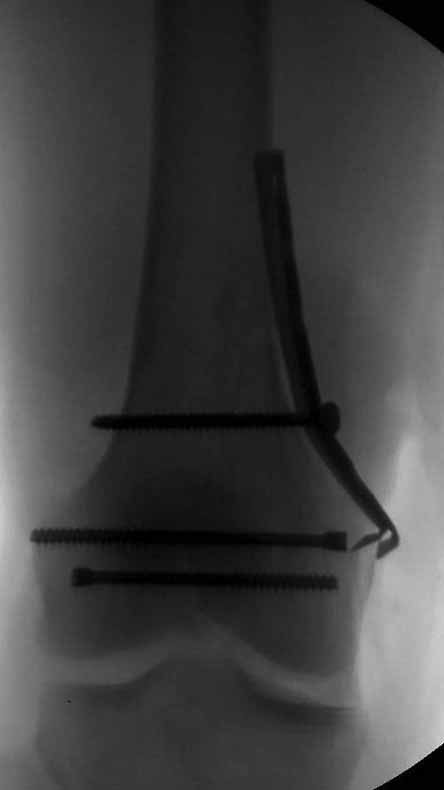

И уже лет шесть мы используем возможность ввести в дистальное овальное отверстие 3 винта, которые именно запираются в этом отверстии, не люфтят, а обеспечивают угловую стабильность - см картинку.

Получается и стабильно, и очень дистально, нижний край отверстия в 3 мм от дистального конца гвоздя.

В приложении пример недавней операции, C3, открытая репозиция, фиксация мыщелков спицами и винтами, ретроградный синтез большеберцовым гвоздем 10,5 мм диаметром, винты 5 мм.

Наш гвоздик, выпускаемый предприятием ЦИТО, тоже скорее из универсальных, хотя и с расширенными возможностями для дистальных переломов. Это овальное отверстие внизу задумывалось как динамическое для высоких переломов, очень дистально его разместили, чтобы не опасаться перелома гвоздя по этому отверстию. А возможность вот такого введения винтов, образующих "сборный клинок", обнаружилась года через 3 его применения.

Но практика показывает, что классификации существуют не зря, и стоит пользоваться ими, а не ориентироваться на абстрактные "максимально низкие переломы". Подавляющее большинство поступающих к нам больных с дистальными переломами - это C1 и С2. И показанный в прошлом сообщении гвоздик прекрасно справляется. Наверно, сгодятся и многие современные гвозди разных производителей, типа RAFN Synthes. А вот при настоящих C3 одним гвоздем не обойтись, нужны как минимум винты мимо, а то и введение на одном уровне нескольких винтов и/или спиц веером...